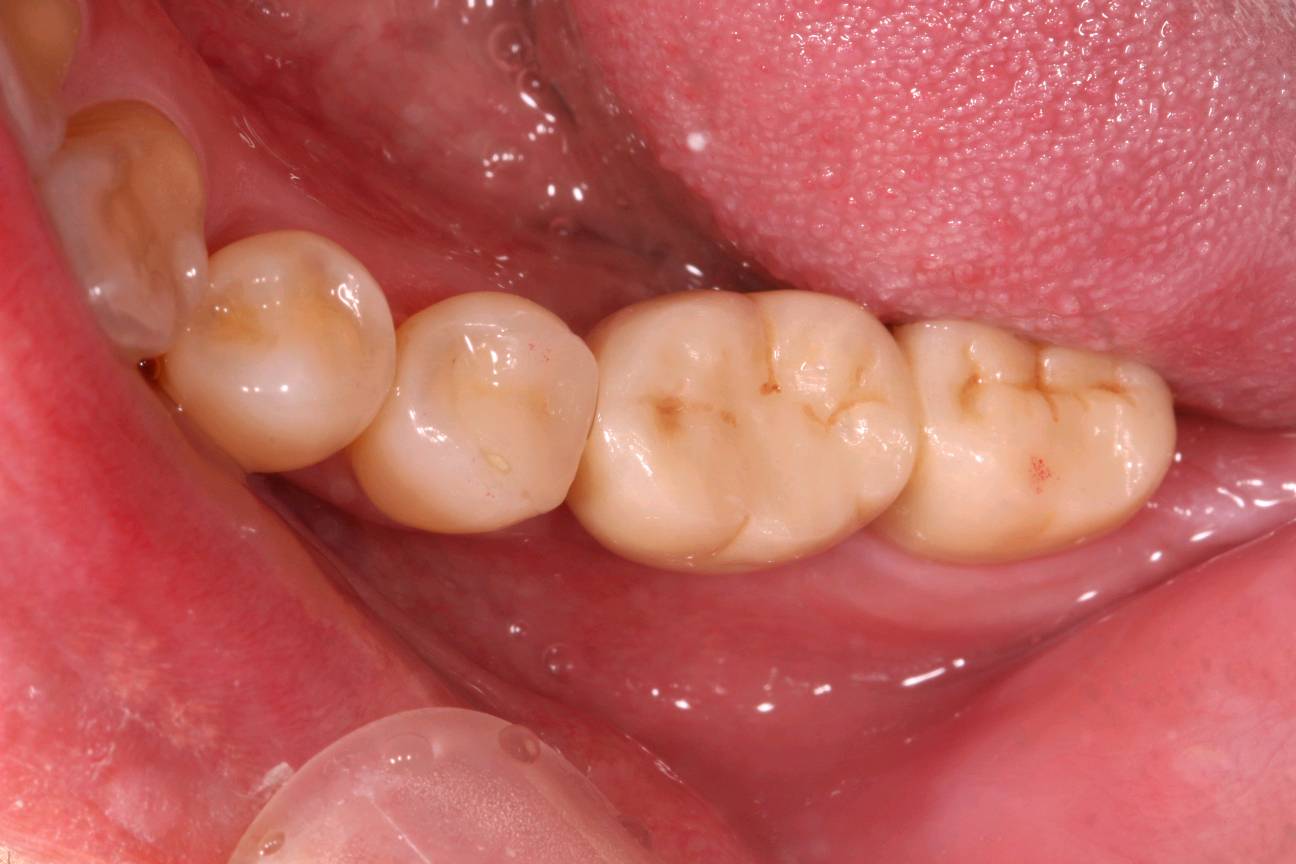

患者男,35岁,右下后牙缺失半年。口内检查:47牙体缺失,缺牙区牙槽嵴中度萎缩,无骨尖。颌龈距离约5mm。46松动+++,牙龈中重度退缩。X线示缺牙区骨密度良好。46牙槽骨吸收至根尖1/3。

术前